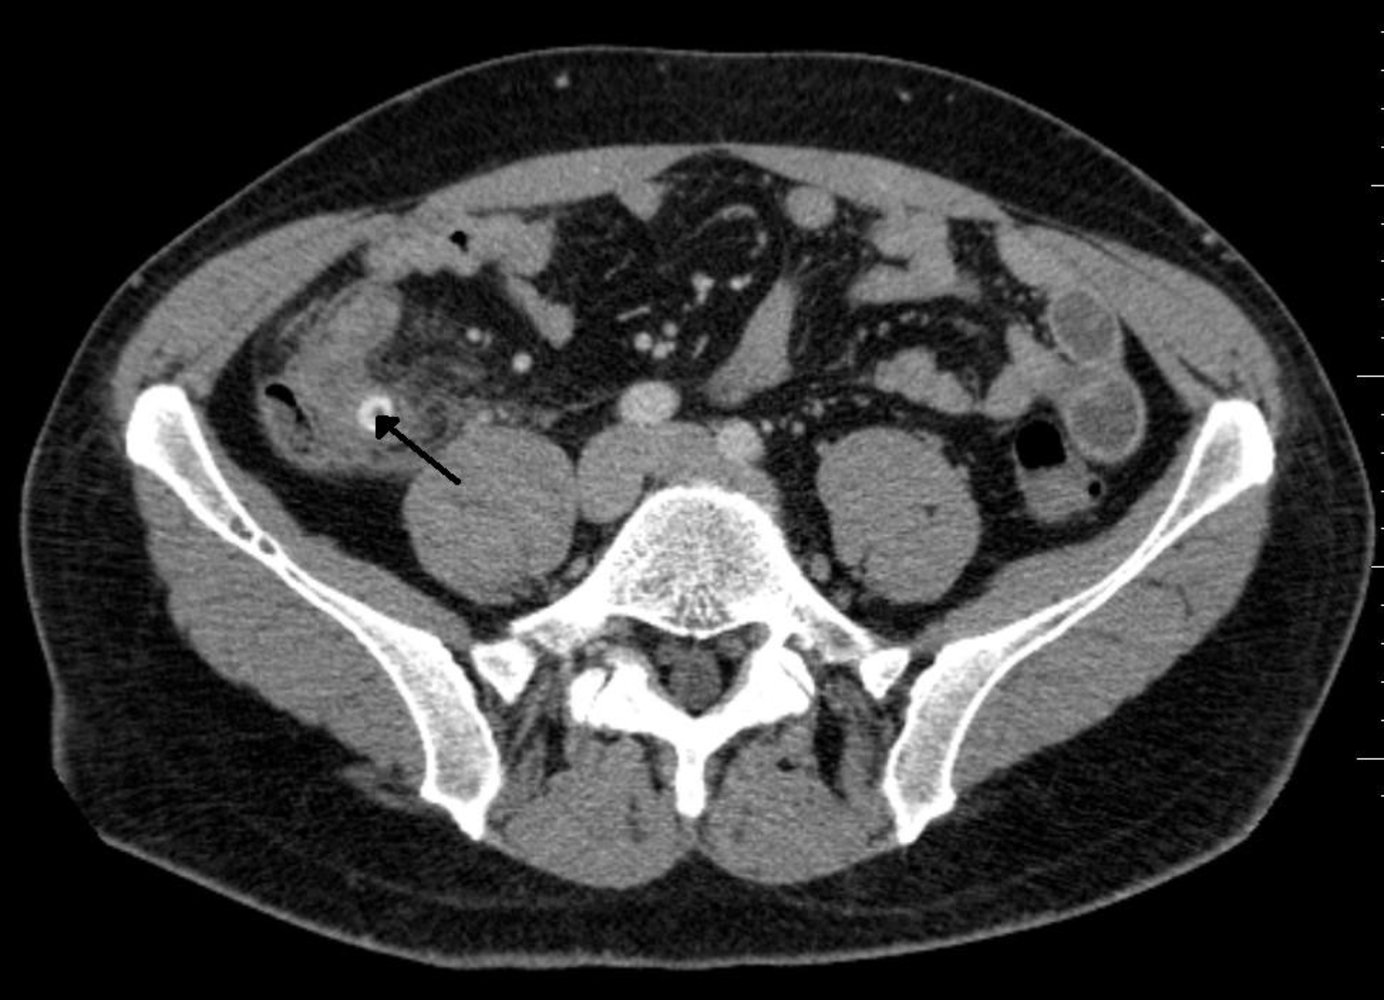

CT abdomen with IV contrast

CT abdomen is the most accurate initial imaging modality for appendicitis. [12][29]

Supportive findings [29]

- Distended appendix (diameter > 6 mm)

- Edematous appendix with periappendiceal fat stranding

- Possible appendiceal fecalith: focal hyperdensity within the appendiceal lumen

- Evidence of complications

- Consider low-dose CT scan (with IV contrast) to minimize radiation exposure. [33][34]

- Consider CT without contrast in patients with contrast allergy. [34]

Adding oral and/or rectal contrast does not improve diagnostic accuracy and may delay diagnosis. [10]